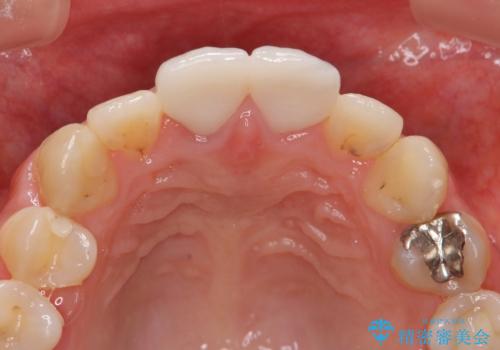

前歯 審美改善セラミック治療

ジルコニアクラウンによる審美性の改善を計画します。

- 24万円(仮歯・ファイバーコア・ジルコニアクラウン)費用は治療当時の料金となります

このような場合金属を使わないジルコニアクラウンを用いた治療を行うことで天然の歯のように審美性を改善することが可能になります。